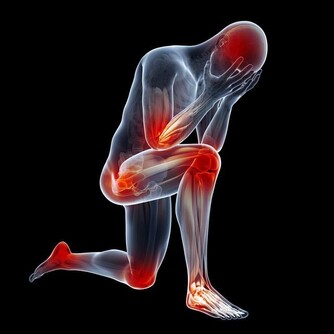

1、胸悶氣短: 一些業主在搬進新家後常常感覺到胸悶氣短、呼吸不暢,但去醫院檢查又沒有發現任何心肺問題,這種情況很有可能是甲醛中毒引起的。胸悶是甲醛中毒常見症狀之一,一般在輕度或中度中毒時出現。所以,如果時常在家中感到胸悶,首先應去醫院排除心臟問題,然後再確定是否是甲醛超標造成的。

2、呼吸系統刺激: 回家開門的一瞬間,家的溫馨氣息就會撲面而來,但新家不是這樣,新業主每次回家聞到的第一縷空氣往往伴隨刺鼻的化學品氣味,怎麼會感受到溫馨呢?這種裝修特有的刺鼻氣體的主要有害成分就是甲醛,多數家庭可在通風一個月時間明顯減輕(注意減輕並不等於消除),但如果通風一個月還沒有改觀,那就應該考慮治理室內空氣污染了。